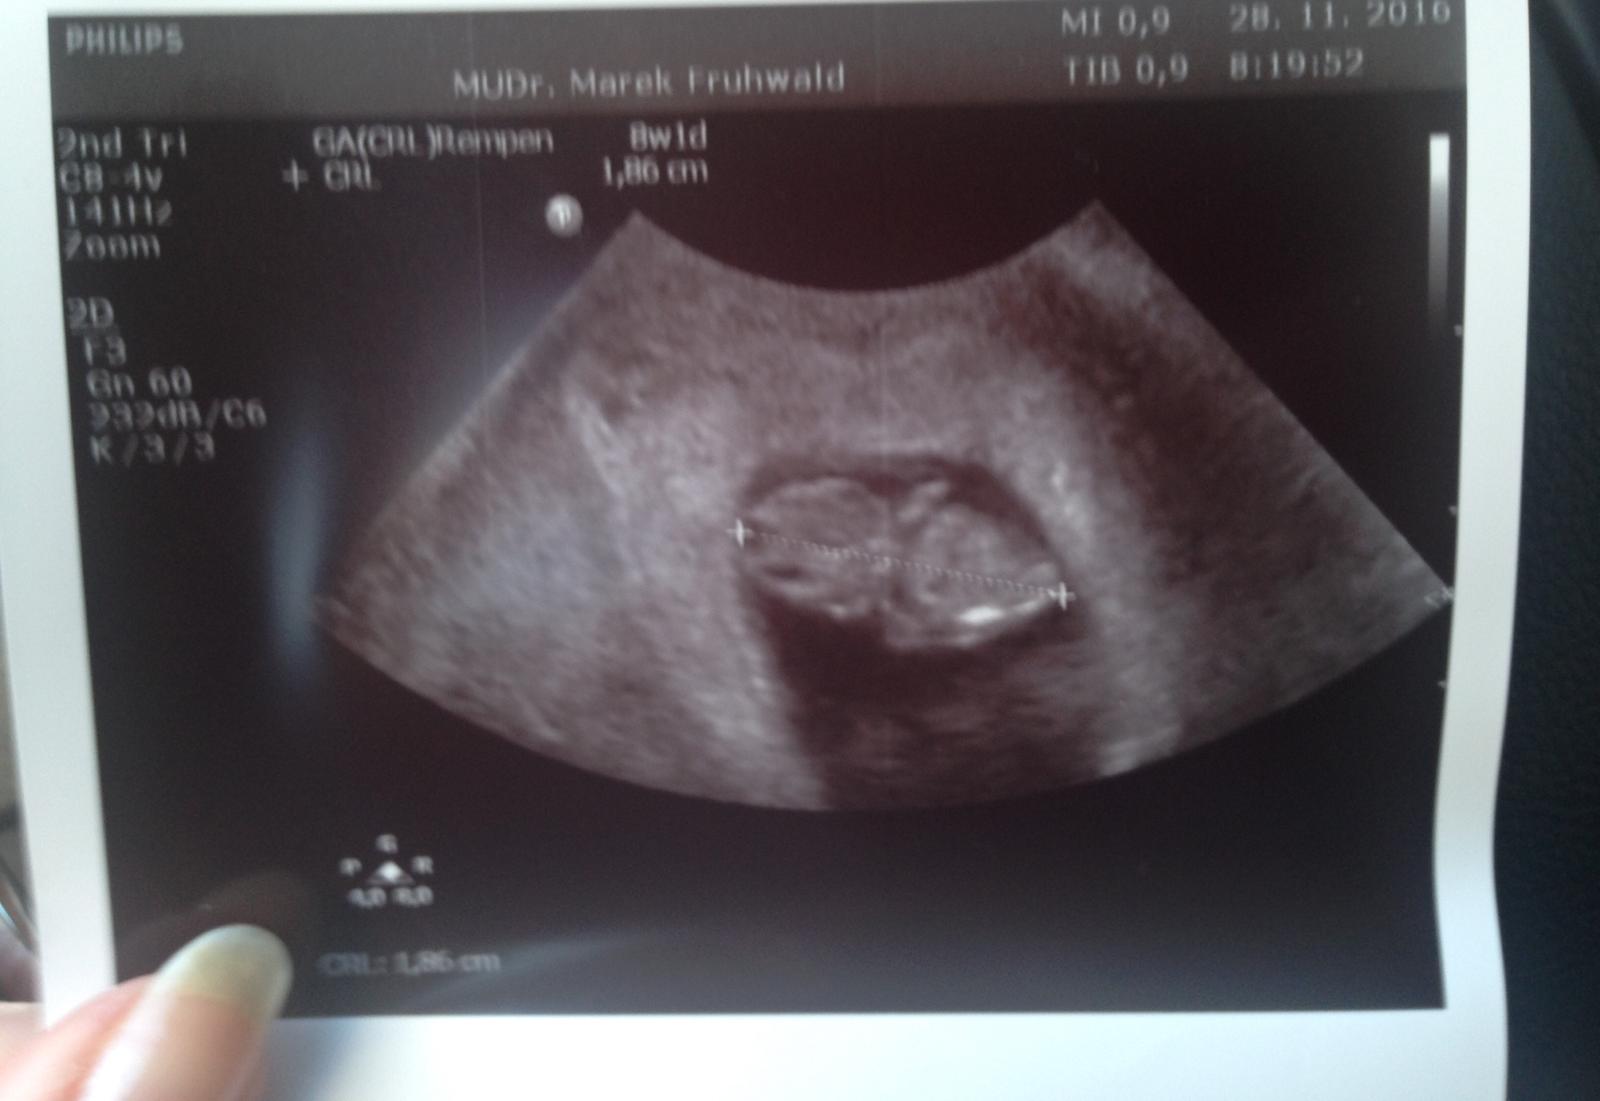

@miriamn76 .... drobcek nam kraaasne podrastol amme skoro 2cm sme uz velkaciky ,rucicky a nozicky su na svojom mieste a pan dr. bol taky zlaty ,ze maminke pre pokoj duse a radost pustil nahlas pulzujuce srdienko a viete co? bilo mi ostosest a maminka samozrejme slzicky v ociach lebo take stastie ake som jej ja do zivota priniesol , to neprekona NIKTO 👶🏼💓

@happymia Srdečne gratulujem. Drobček je už naozaj veľkáč. Prajem krásne tehotenstvo...